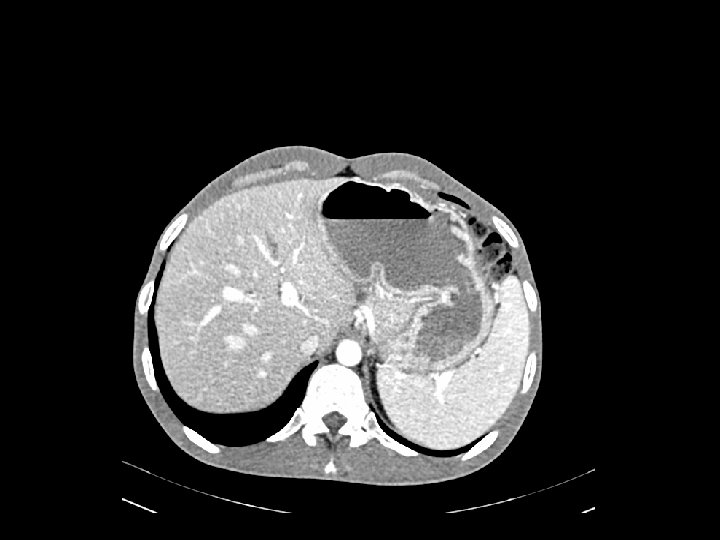

Caso Clínico 1 Diciembre 2012: Vómitos intermitentes y dolor abdominal Urgencias Ecografía abdominal 15/4/2013: hi gado de taman o normal con ecogenicidad homogenea, sin LOES ni dilatacio n dela via biliar intrahepa tica. Vesi cula alitia sica. Bazo y rin ones normales. Aorta normal. No li quido libre.

Caso Clínico 1 Urgencias (22 Agosto 2013): Dolor abdominal agudo y vómitos A la exploración destacaba abdomen distendido, doloroso a la palpación con defensa